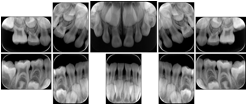

OO.1.2 Ophthalmology

1. A patient in rural Canada visits a general ophthalmologist and is found to have diabetic macular edema. The general ophthalmologist would like to discuss the case with a retina specialist before performing laser surgery. A fluorescein angiogram is done with multiple retinal images taken in a timed series after an intravenous injection. The images along with a Structured Display are shared via a Health Information Exchange with a retina specialist in Calgary, who opens them using his Ophthalmology EMR software and consults via phone with the general ophthalmologist. Both physicians view the images in the same layout so the retina specialist can provide accurate guidance for treating the patient.

2. A patient in rural Iowa visits his primary care physician for management of diabetes. Three non-mydriatic (patient's eyes are not dilated) photographs are taken of the back of each eye, and forwarded electronically along with a Structured Display to an ophthalmologist in Iowa City. The ophthalmologist reads the photos in an agreed upon layout so there is no mistake about what portion of which eye is being viewed. The ophthalmologist is able to tell the primary care physician that his patient does not need to come to Iowa City for face to face ophthalmologic care, but that there is a particular view of the left eye that should be photographed again in 6 months.

Ophthalmic Retinal Study Structured Display

Figure OO-3. Ophthalmic Retinal Study Structured Display